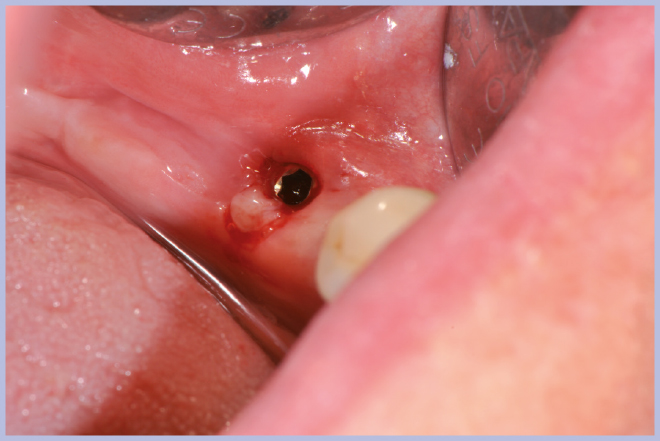

- Figg. 17, 18 – Passaggio dei mucotomi guidati dalla mascherina chirurgica

- Fig. 18

- Figg. 19, 20 – Passaggio fresa Zero1 attraverso la boccola per impianto Exacone® Ø 3,3

- Fig. 20

- Fig. 21 – Cambio carrier impianto per posizionamento guidato

- Fig. 22 – Posizionamento impianto Exacone® Ø 3,3 con tappo basso